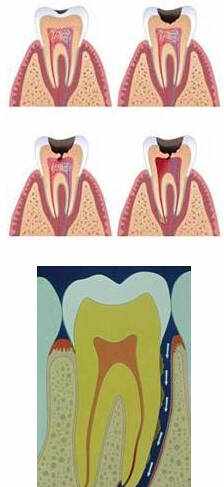

龋齿的发展

1

白斑

牙垢沉积在牙齿表面,牙齿表面珐琅质被牙垢中的细菌消化糖后,排泄出来的酸溶解,就发生脱矿了。

牙齿中的钙减少了,色泽就变成白粉笔色(白琧)感觉了。

2

釉质龋

脱矿没有及时修复,牙齿表面开始缺损,就成为我们说的蛀牙、牙洞了。

早期的龋齿患者是没有感觉的,因此容易出现拖延,导致错过治疗的最佳时期。

3

牙本质或牙骨质龋

随着龋坏的发展,逐渐出现喝冷热水或者进食时敏感不适。

4

深龋

此时如果不及时治疗龋坏,将继续向深层牙体组织发展,就会出现遇冷遇热疼痛,之后形成明显龋洞。

当有食物进入龋洞后常导致患牙疼痛,此时已发展为深龋,换言之,龋洞已经很深,洞底与牙神经之间的距离已经非常近。

5

牙髓炎

如果此时依然没有及时治疗,龋坏里的细菌会入侵牙神经。

这会导致:牙神经发炎,牙齿出现自发疼痛,并且逐渐加剧,重者夜间睡眠受到影响,需要口含冷水才能使疼痛稍有缓解。

此时,疾病的名称为牙髓炎。

6

根尖周炎

疾病至此,如果患者仍旧未及时治疗,牙神经内的细菌会继续向深层入侵,到达牙根的根尖区域,此时称为根尖周炎。

患牙的自发疼痛减弱,牙根区域出现跳痛,牙齿咬合疼痛,并出现患牙伸长浮起的感觉。

根管治疗的过程:(见图)

根管预备--去除牙齿腐坏组织,打开牙髓腔,用一套金属锉将根管扩大并用消毒药水将其中的感染碎屑冲洗出来。

根管充填--使用根管充填材料将清理干净后的根管系统封闭起来。

根管消毒封药--如果根管里有感染残留,医生可能会在根管内封抗菌药,下次就诊时根据感染是否得到控制,决定是否做根管充填。

根管治疗的过程:(见图)

根管预备--去除牙齿腐坏组织,打开牙髓腔,用一套金属锉将根管扩大并用消毒药水将其中的感染碎屑冲洗出来。

根管充填--使用根管充填材料将清理干净后的根管系统封闭起来。

根管消毒封药--如果根管里有感染残留,医生可能会在根管内封抗菌药,下次就诊时根据感染是否得到控制,决定是否做根管充填。